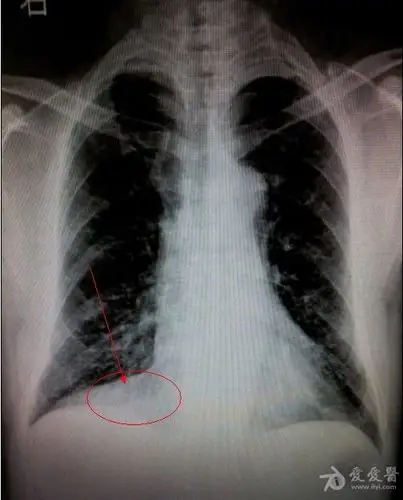

注意右侧心膈角,右下叶不张  的诊断成立.影像科的大夫会看图说话